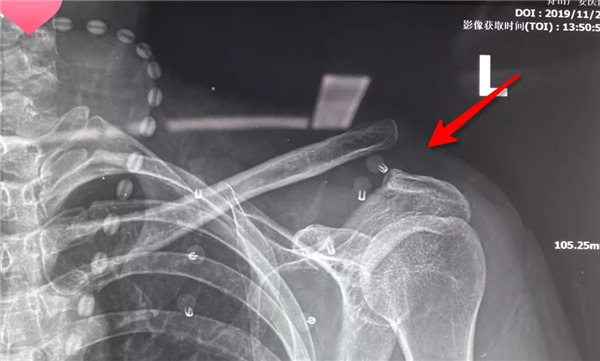

經(jīng)患者與家屬同意后,羅軍主任手術(shù)團(tuán)隊成功為患者實(shí)施了左肩鎖關(guān)節(jié)復(fù)位Y型Endobutton固定系統(tǒng)固定術(shù)。手術(shù)只用50分鐘時間。術(shù)后X片復(fù)查顯示肩鎖關(guān)節(jié)脫位完全復(fù)位,術(shù)后第二天楊女士在康復(fù)醫(yī)師指導(dǎo)下開始進(jìn)行左肩關(guān)節(jié)功能鍛煉,楊女士左肩部疼痛明顯減輕,左肩關(guān)節(jié)可抬起、前舉,功能較術(shù)前明顯改善,楊女士大約再經(jīng)過3-4周康復(fù)訓(xùn)練左肩關(guān)節(jié)功能可恢復(fù)正常。

術(shù)后拍片